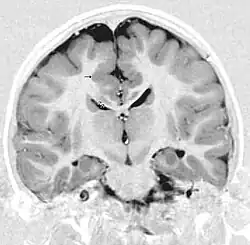

Das Bildgebendes Verfahren der Wahl ist die Kernspintomographie.[6][10][9] Das heterotope Gewebe entspricht in seiner Signalgebung in allen Sequenzen der von grauer Substanz. In der fMRT kann mit BOLD-Kontrast eine Aktivierung der Heterotopien gezeigt werden.[11]